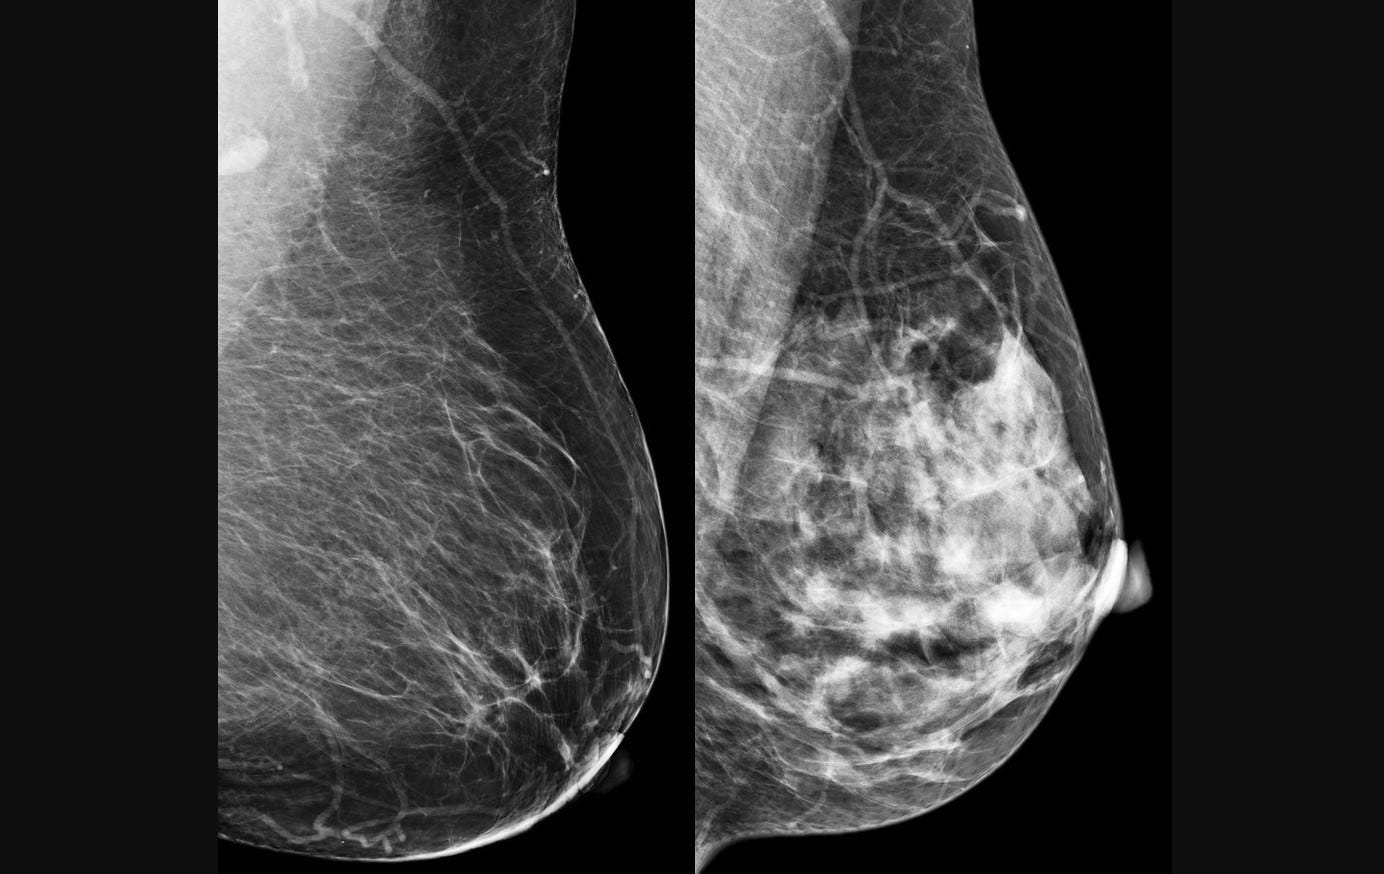

O câncer de mama foi escolhido como alvo para teste do modelo computacional porque é o tipo mais comum entre mulheres no mundo, com 2,3 milhões de casos e 670 mil mortes registradas em 2022 (imagem: CDC/reprodução)

O câncer de mama foi escolhido como alvo para teste do modelo computacional porque é o tipo mais comum entre mulheres no mundo, com 2,3 milhões de casos e 670 mil mortes registradas em 2022. A detecção precoce é crucial para aumentar as chances de cura e sobrevida. No entanto, métodos tradicionais, como a mamografia, dependem fortemente da interpretação humana, o que pode levar a variações no diagnóstico. “Apesar de ser teoricamente simples de acompanhar, a mamografia ainda é um exame cuja interpretação depende muito do profissional que realiza o procedimento”, diz Papa.